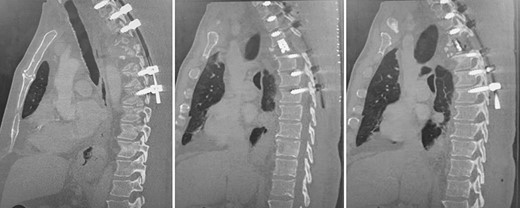

Post-operative, sagittal CT images of the T1–T7 pedicle screw fixation and expandable titanium cage in situ.